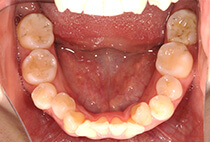

治療前